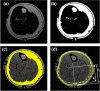

Despite the potential for biomechanical conditioning with prosthetic use, the soft tissues of residual limbs following lower-limb amputation are vulnerable to damage. Imaging studies revealing morphological changes in these soft tissues have not distinguished between superficial and intramuscular adipose distribution, despite the recognition that intramuscular fat levels indicate reduced tolerance to mechanical loading. Furthermore, it is unclear how these changes may alter tissue tone and stiffness, which are key features in prosthetic socket design. This study was designed to compare the morphology and biomechanical response of limb tissues to mechanical loading in individuals with and without transtibial amputation, using magnetic resonance imaging in combination with tissue structural stiffness. The results revealed higher adipose infiltrating muscle in residual limbs than in intact limbs (residual: median 2.5% (range 0.2-8.9%); contralateral: 1.7% (0.1-5.1%); control: 0.9% (0.4-1.3%)), indicating muscle atrophy and adaptation post-amputation. The intramuscular adipose content correlated negatively with daily socket use, although there was no association with time post-amputation. Residual limbs were significantly stiffer than intact limbs at the patellar tendon site, which plays a key role in load transfer across the limb-prosthesis interface. The tissue changes following amputation have relevance in the clinical understanding of prosthetic socket design variables and soft tissue damage risk in this vulnerable group.